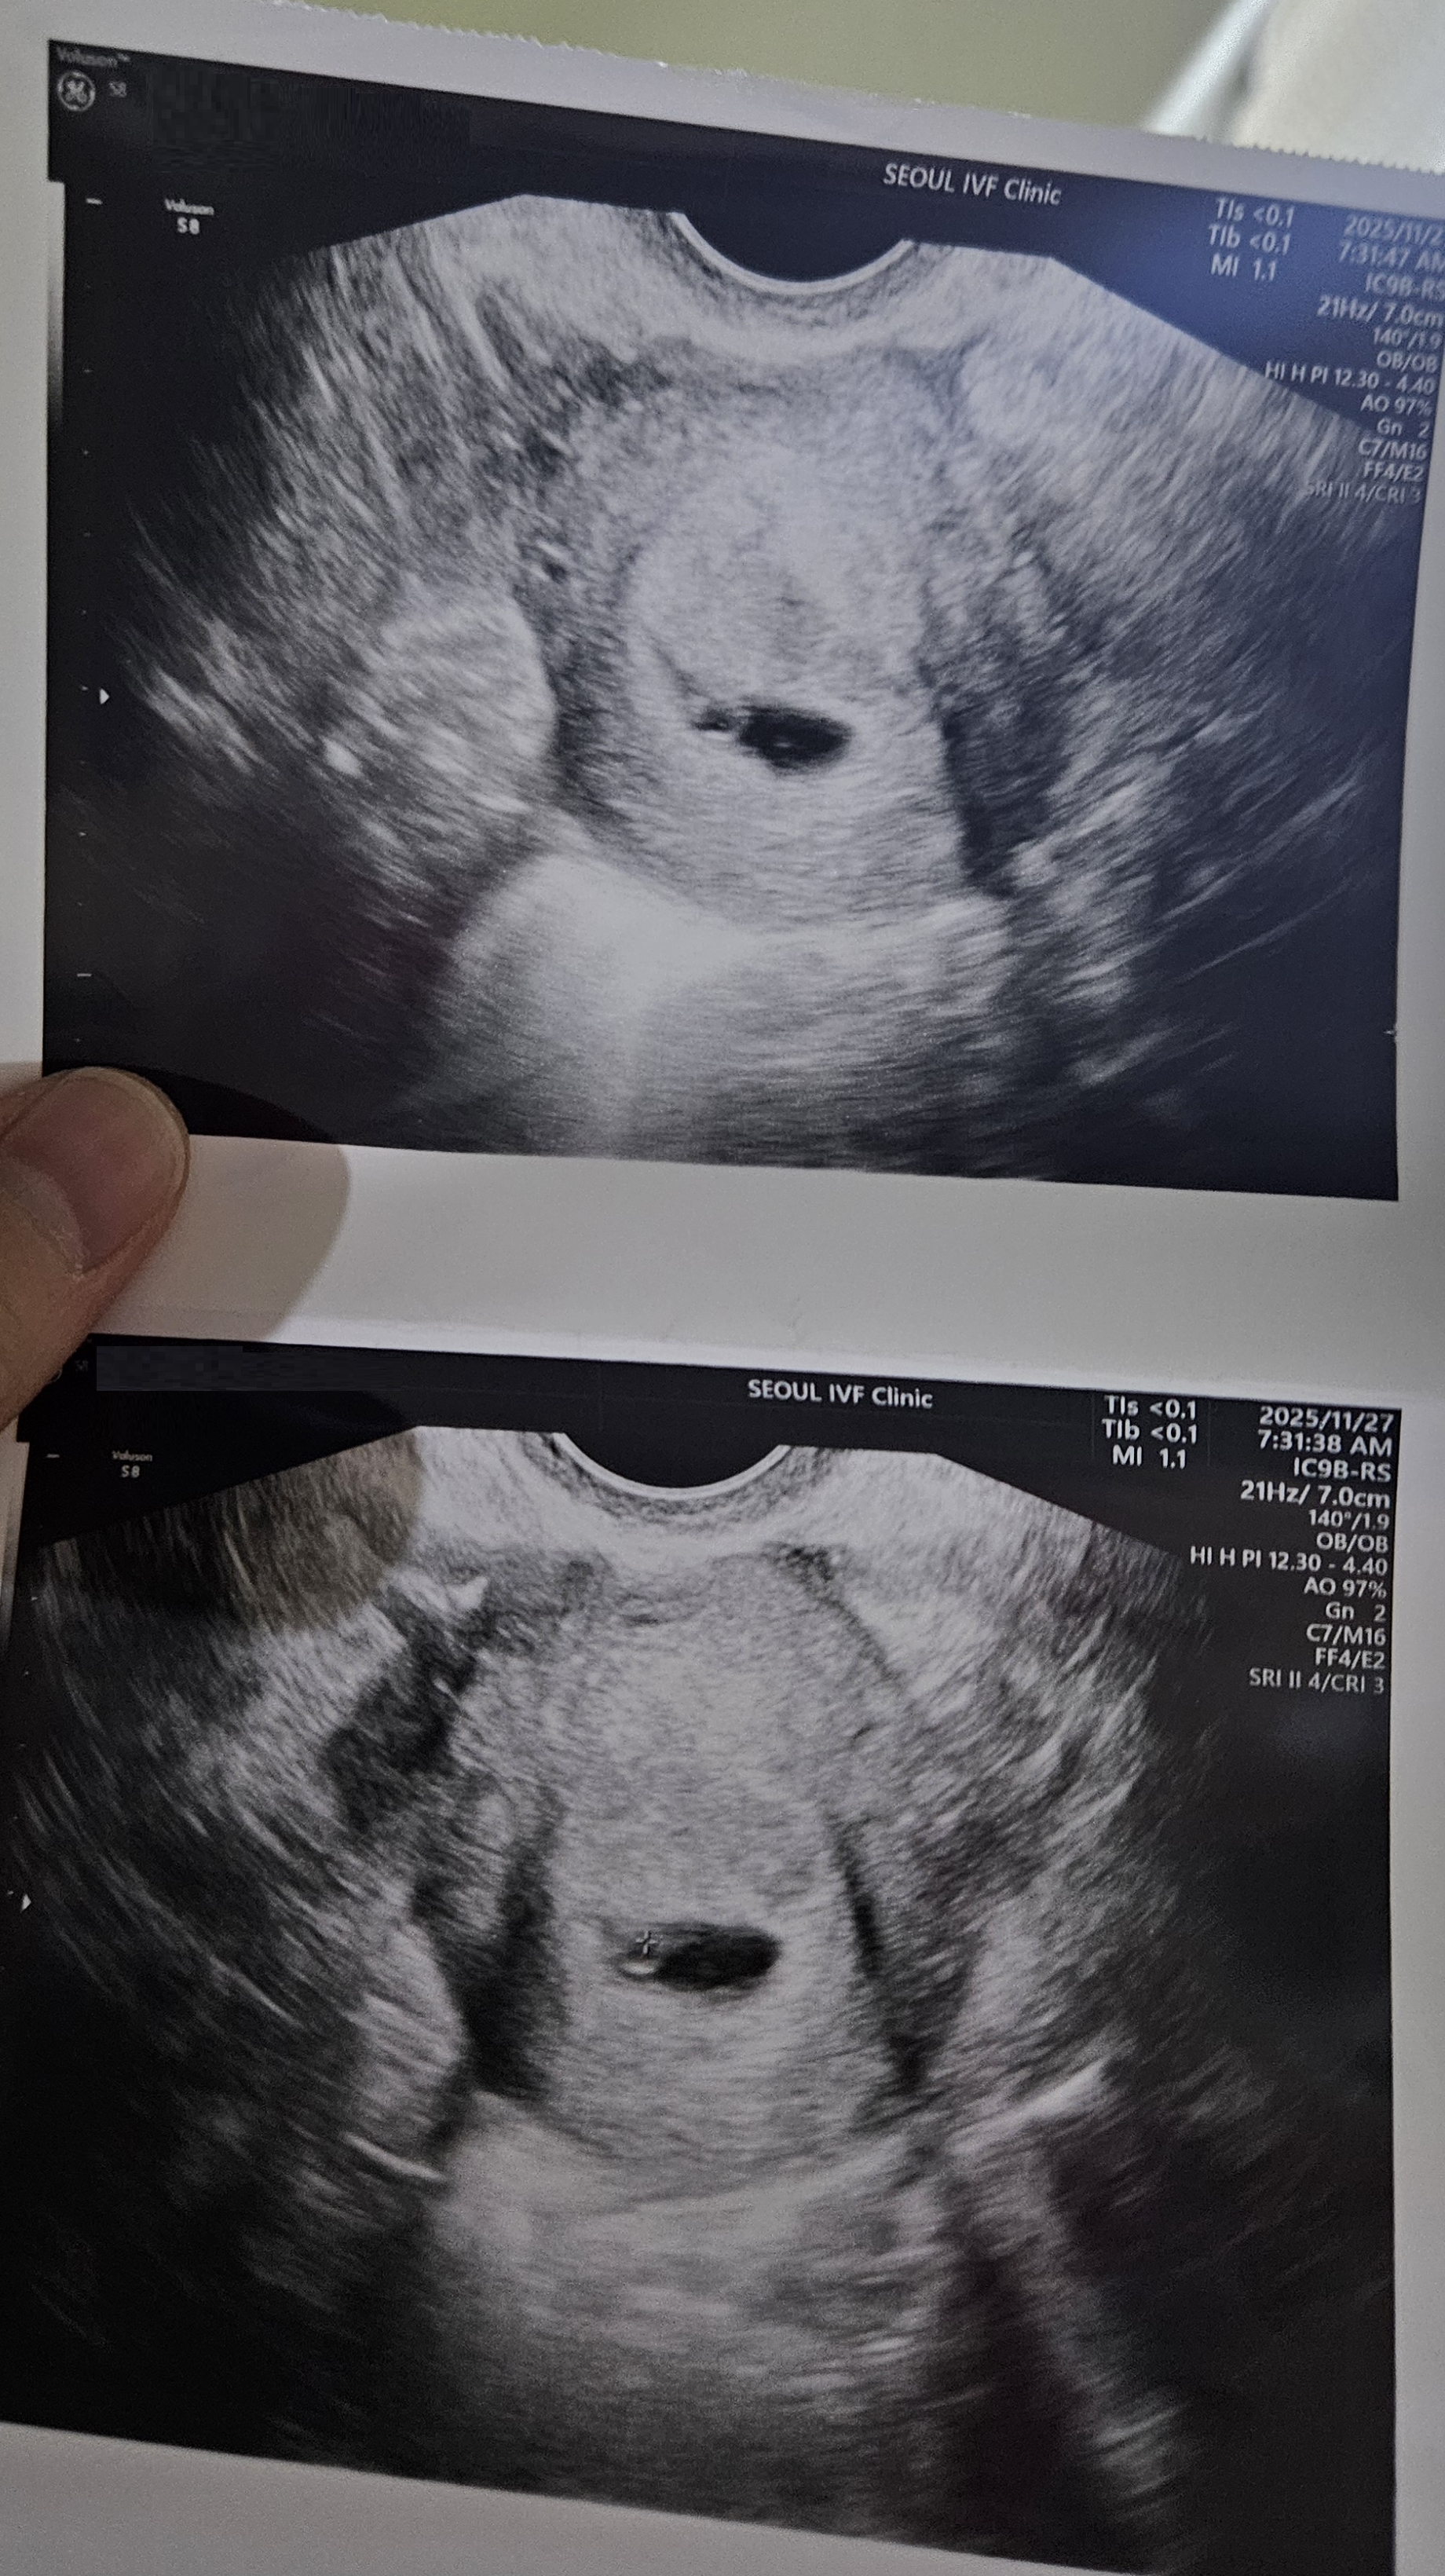

| 가슴 떨리는 임신 이야기를 공유해 주세요. | 임신 소식을 들었을 때도 기뻤지만, 아기의 심장소리를 처음 들었을 때의 감동은 말로 표현하기 어려울 정도였습니다. 긴 기다림 끝에 만난 순간이었습니다. |

| 치료 도중 느꼈던 가장 기뻤던 순간과 절망적인 것들은 무엇인가요? 잊지 못할 경험이 있나요? | 가장 기뻤던 순간은 심장소리를 들었을 때였고, 가장 힘들었던 순간은 인공수정이 실패했을 때였습니다. 희망과 실망이 반복되는 기다림의 연속이었습니다. |